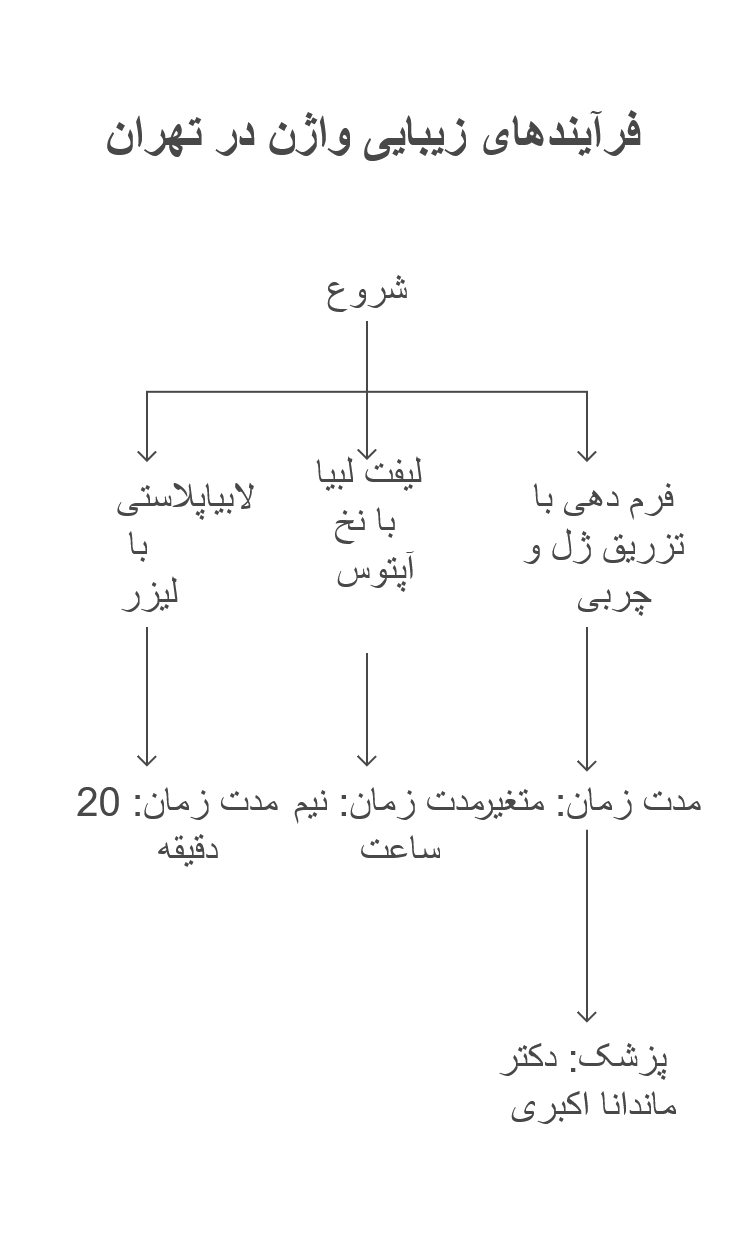

تزریق ژل به واژن یا بیکینی – بهترین پزشک در تهران – بهترین کلینیک در تهران

خوشفرم کردن واژن با تزریق ژل به واژن یا تزریق ژل به بیکینی:

فرم دهی به واژن زمانی فکر برخی بانوان را درگیر میکند که با افزایش سن یا زایمان یا کاهش وزن واژن حالت خود را از دست می دهد و از فرم طبیعی خود خارج می شود لذا برای درمان این مشکل جهت فرمدهی به واژن خود اقدام مینمایند.

برای فرم دهی به واژن چندین پروسیجر بسیار تاثیرگذار انجام می شود که در کوتاهترین زمان نتایج قابل توجی در بر دارد.

- لابیاپلاستی با لیزر در تهران توسط دکتر ماندانا اکبری

- لیفت لبیا با نخ جوانساز آپتوس در تهران توسط دکتر ماندانا اکبری

- فرم دهی به واژن با تزریق ژل و چربی به واژن در تهران توسط دکتر ماندانا اکبری

موارد فوق الذکر از مهمترین اعمال زیبایی واژن و لبیاها است که در تهران توسط بهترین جراح زیبایی انجام می شود.

عمل زیبایی واژن چقدر طول می کشد؟

- لابیاپلاستی با لیزر حدود 20 دقیقه طول می کشد البته بسته به میزان اندازه لبیا و ضخامت لبیا یک مقدار متفاوت است.

- لیفت لبیا با نخ آپتوس حدود نیم ساعت طول میکشد.

- فرم دهی به واژن با تزریق ژل و چربی بسته به کیس های مختلف متفاوت است.

یکی از بهترین پزشکان و جراحان زیبایی زنان در تهران در منطقه پاسداران تهران در کلینیک ایران لابیاپلاستی خانم دکتر ماندانا اکبری متخصص جراحی زنان و فوق تخصص زیبایی زنان و لابیاپلاستی با لیزر در تهران است که می توانید از طریق شماره های زیر با مشاوران کلینیک در ارتباط باشید.